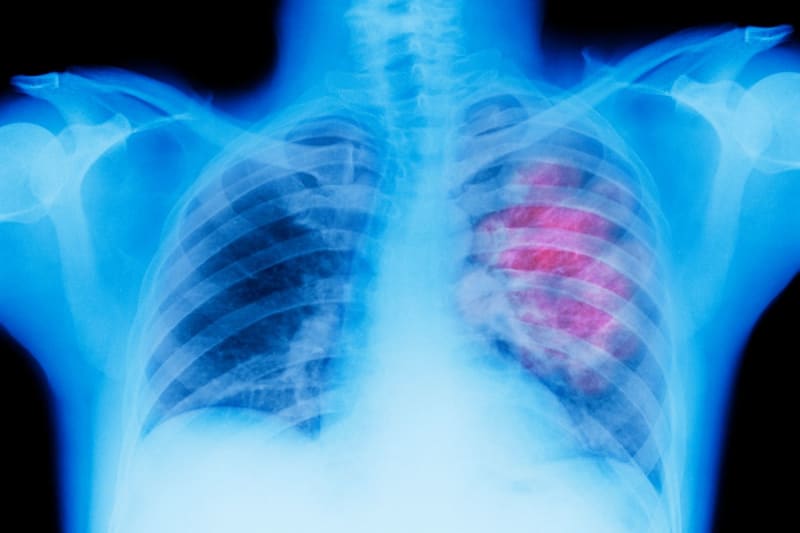

The NHS is now piloting a breakthrough technology that combines artificial intelligence with a robotic catheter to detect tiny lung tumors previously impossible to reach. The thin tube, inserted through the patient's throat, can navigate to nodules as small as 6mm hidden deep in lung tissue.

Here's how it works: AI analyzes lung scans to identify suspicious spots, then guides the robotic catheter to take precise biopsies in a single procedure. Before this technology, reaching these deep tumors required weeks of invasive testing, or the cancers went undetected until they grew larger and more dangerous.